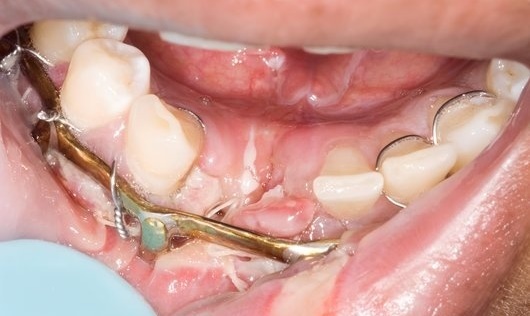

Photos of Archbars that have been wired to teeth. Elastics or wires are used to bring the archbars (and hence, teeth and jaws) together.

The archbars are wired to the teeth to keep them in place. This has the knock-on effects of:

- Staining to teeth

- Early decay around the necks of the teeth

- Bleeding that is easily provoked with tooth brushing of bleeding from the gums

- (Marked) Gum recession leading to dentine sensitivity to hot and cold

- Extrusion of the teeth, with the occlusion needing time to bed in